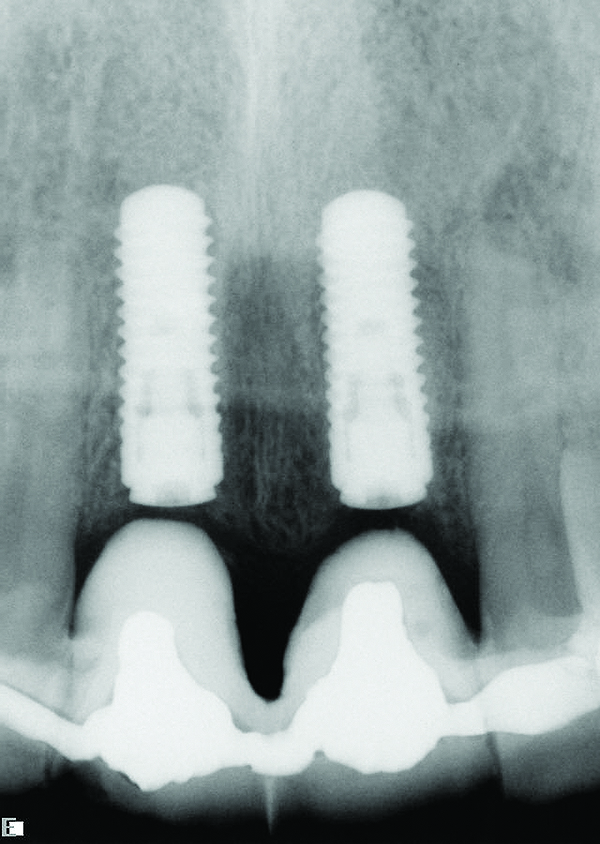

The DICOM (digital imaging and communications in medicine) images are then imported from the CBCT files into one of many commercially available implant-planning software programs. The surgeon and restorative dentist can then collaborate in choosing the precise position, angulation, and depth of implant placement, as well as the implant type, based upon a desired prosthetic outcome. Rosenfeld et al coined the term “collaborative accountability” to describe the pretreatment analysis and subsequent negotiated compromises between surgical and restorative colleagues on implant positioning and restorative design based upon anatomic limitations and the team’s willingness and ability to overcome them.3 Additionally, this pretreatment evaluation is invaluable in creating realistic patient expectations. Figure 1 through Figure 6 demonstrate a case showing 3-dimensional (3-D) presurgical planning, radiographic evidence of the plan’s execution, and 2-year follow-up. As a result of 3-D planning and subsequent guided implant surgery, the patient wound up with a pleasing, nature-like esthetic outcome (Figure 5).

Fig 1. Pretreatment plan for guided implant surgery to replace teeth Nos. 8 and 9.

Figure 1

Fig 2. Cross-sectional view of proposed implant

position. Note that the plan allows the restorative doctors and surgeon to confirm the implants’ position, inclination, depth, and

emergence.

Figure 2

Fig 3. Radiograph confirming that the implant placement matched the presurgical plan.

Figure 3